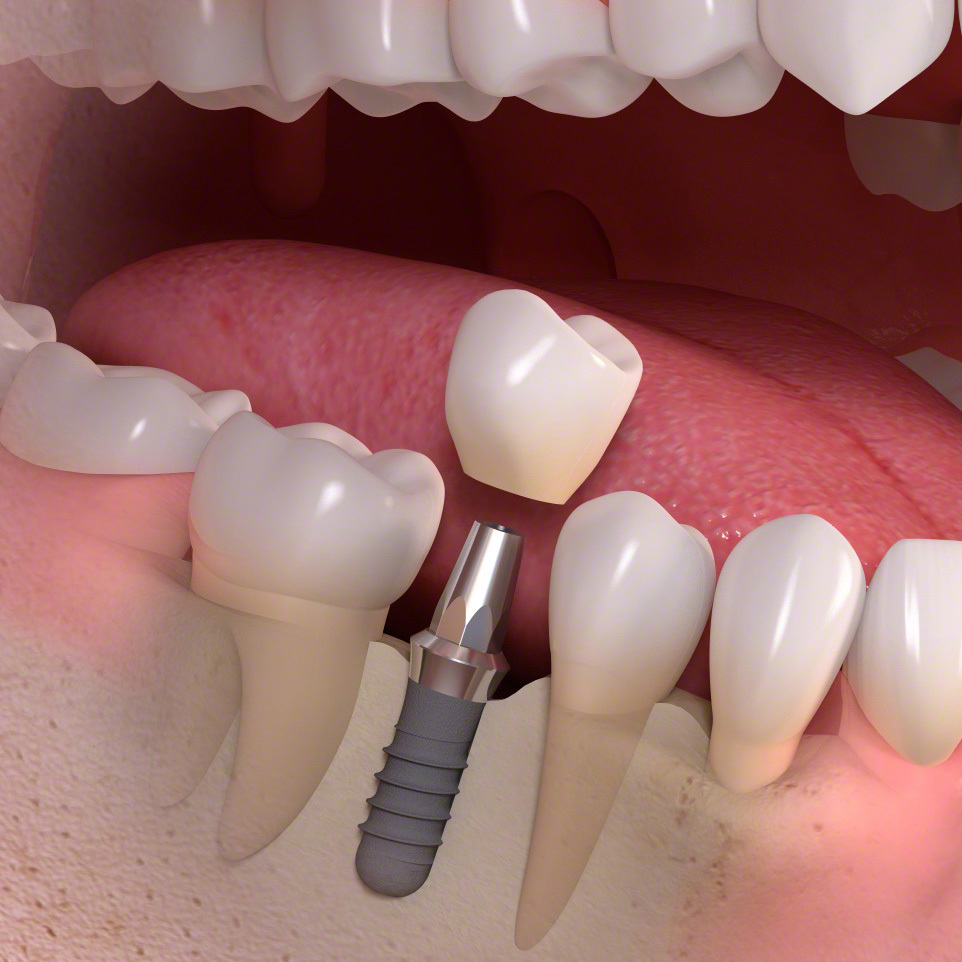

歯科インプラントとは、歯を失った部分に人工歯根(主にチタン製)を外科的に埋め込み、その上にセラミックなどで作られた人工の歯を取り付けて、機能と見た目を回復する治療法です。

その後、一次手術としてインプラント体(フィクスチャー)を顎の骨に埋入し、数か月の治癒期間を経て骨としっかり結合させます。治癒後には二次手術を行い、歯肉からインプラントの上部構造を露出させます。なお、骨や歯肉の状態が良好な場合には、一次手術と二次手術を同時に行う「1回法」が選択されることもあります。

傷口が治った後に精密な型取りを行い、上部構造(人工歯)を製作・装着します。

インプラント構造

インプラントは、人工歯根(いわゆるインプラント)・支台(アバットメント)・人工歯(クラウン)、3つの部品で構成されています。